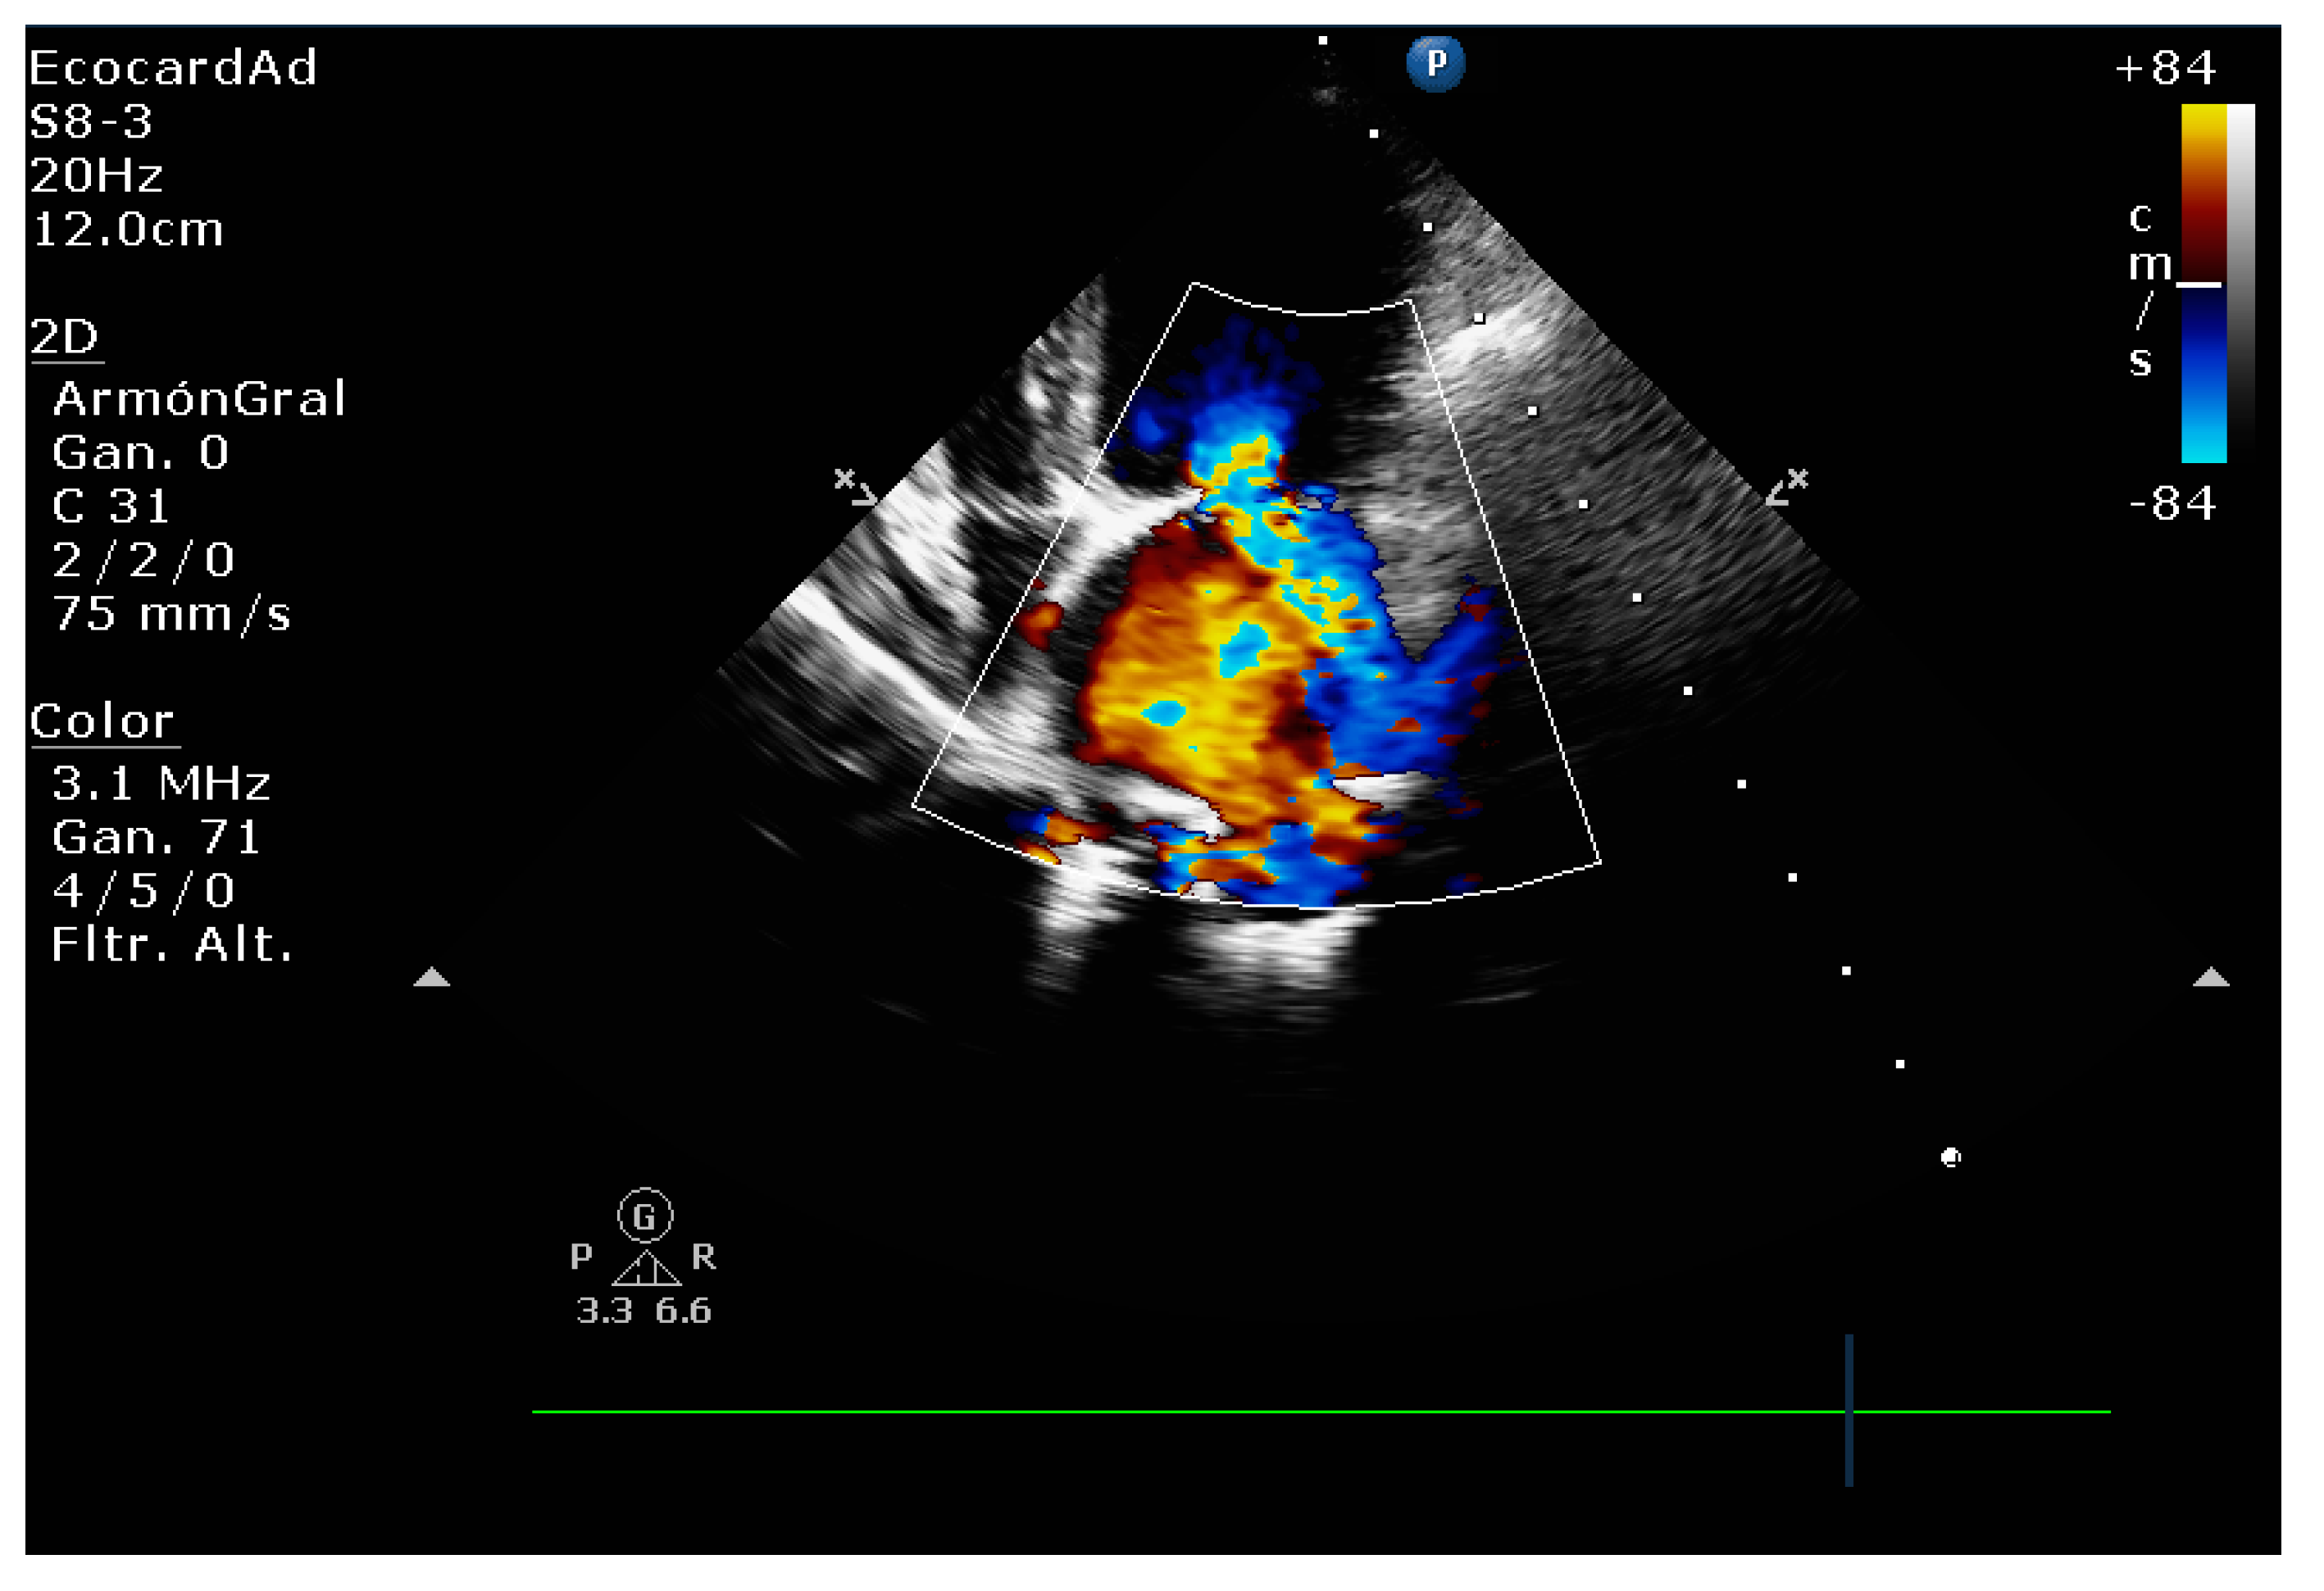

4.4. Comparative Assessment of Mitral Regurgitation Severity

4.5. Mitral Regurgitation Quantification in the Canine Model

4.8.1. Evaluation of the Regurgitant Area

4.8.2. Presence of Vena Contracta

- Muzzi, R.A.; de Araújo, R.B.; Muzzi, L.A.; Pena, J.L.; Silva, E.F. Regurgitant jet area by Doppler color flow mapping: Quantitative assessment of mitral regurgitation severity in dogs. J. Vet. Cardiol. 2003, 5, 33–38. [Google Scholar] [CrossRef]

| Color flow imaging of the mitral regurgitation jet area | The most commonly used technique for assessing severity in dogs. The former method is not used in humans as it is not considered reliable for determining the severity of mitral insufficiency. |